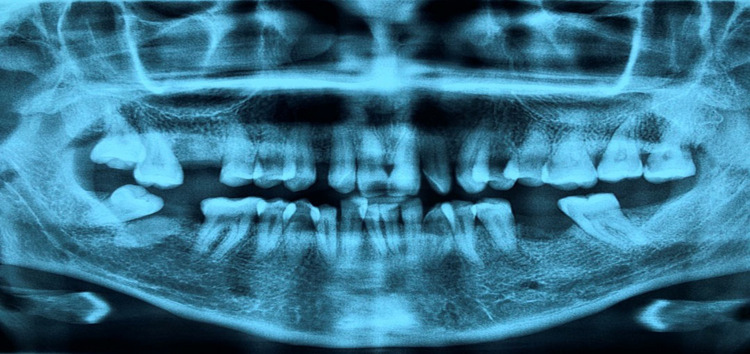

Hereditary gingival fibromatosis (HGF) is an uncommon genetic condition marked by gradual and progressive overgrowth of fibrous tissue in the gums, which is benign in nature. It is a genetic disorder inherited in an autosomal dominant pattern, known for its considerable genetic diversity. The marginal, attached, and interdental gingivae are affected by this condition. The affected area appears pink, does not bleed easily, and exhibits a firm, fibrotic texture. Additionally, it displays a hard, widespread nodular growth that is smooth to stippled and has little bleeding tendency. Nevertheless, in certain instances, the enlargement may feel so dense and firm that it resembles bone upon palpation. Accordingly, esthetics and functions related to a healthy gingiva is also affected. The choice of treatment modality often depends on factors such as the severity of gingival overgrowth, available resources, and patient-specific considerations. Laser techniques and electrosurgery have emerged as valuable options, providing benefits like reduced discomfort and enhanced precision. However, traditional surgical methods remain highly effective, particularly when advanced technologies are not available. This article reports on three cases of hereditary gingival fibromatosis (HGF) treated with conventional gingivectomy, flap procedures, and resective osseous surgery (osteoplasty and osteotomy). The aim is to support the efficacy of these interventions in addressing patient complaints and preparing the groundwork for managing additional issues, such as speech and mastication difficulties, delayed eruption of permanent teeth, and malocclusion. The surgical treatment led to significant improvements: masticatory function was markedly enhanced, aesthetic outcomes were notably better, and oral hygiene significantly improved. Additionally, the procedures created favorable conditions for future treatments, including orthodontics, implants, or prosthetics, by providing a more manageable and functional oral environment.